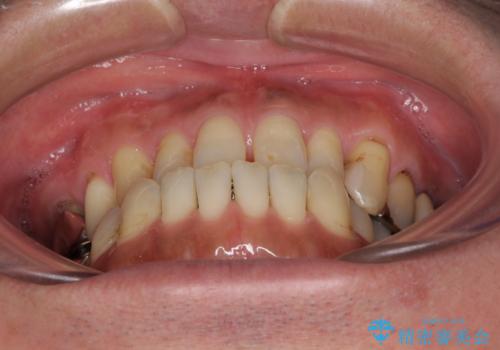

前歯の反対咬合をワイヤー矯正で改善して噛みやすく

- 咬み合わせの悪さを気にして来院された患者様です。

来院当初は、奥歯の銀歯が問題で咬み合わせが悪いと思っていらっしゃいましたが、前歯の反対咬合を改善することが最優先とご説明し、矯正治療を行うこととしました。

奥歯には抜歯が必要な歯があったため、事前に抜歯を行い、その後ワイヤー装置にて治療を開始しました。